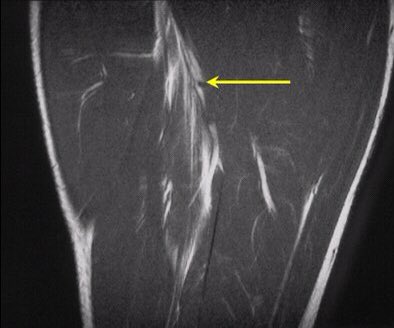

النوع الثاني: تمزق في العضلة الخلفية للفخذ بعد إطالة عالية ومفاجئة للعضلة.

ويحدث غالباً في منطقة الوتر مع التقاءه بعظمة الحوض من الأعلى.

- الوتر هي المنطقة البيضاء بالصورة.